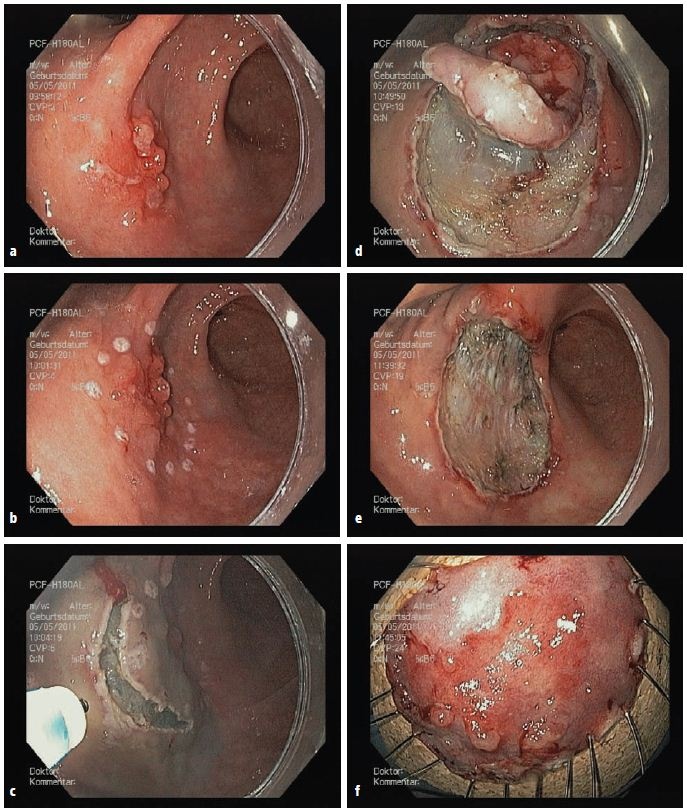

Die in Japan und anderen fernöstlichen Ländern bereits seit Längerem etablierte ESD erfolgt ebenso wie eine Magenspiegelung mithilfe eines flexi¬blen Endoskops über den Mund des Patienten. Über dieses wird die Mukosa im Bereich des Tumors mit Kochsalzlösung unterspritzt. Diese hebt sich dadurch von den unterliegenden Gewebsschichten ab. Anschließend umschneidet der Endoskopiker großflächig den erkrankten Bereich und durchtrennt die Submukosa. Auf diese Weise ermöglicht es die ESD, auch großflächigere Magentumore mit einem Durchmesser von mehr als 20 mm in einem Stück zu entfernen.